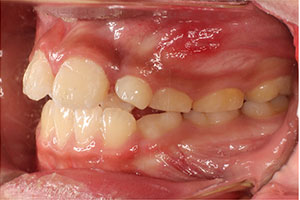

こちらの初診(男性)の患者さんは、開咬合 / 叢生歯列の症状がありました。

1期治療 8歳9ヶ月 2期治療 12歳4ヶ月から治療を開始し、1期治療 7ヶ月 2期治療 2年5ヶ月の間、スタンダードエッジワイズ法(与五沢エッジワイズシステム)を用い矯正治療を行いました。

| 症例分類 | 開咬合 / 叢生歯列 / 偏位咬合 | |||||||||||||||||||||||||||||||||||||||||||||||||||||||||||

| 動的治療期間 | 1期治療 7ヶ月 2期治療 2年5ヶ月 | |||||||||||||||||||||||||||||||||||||||||||||||||||||||||||